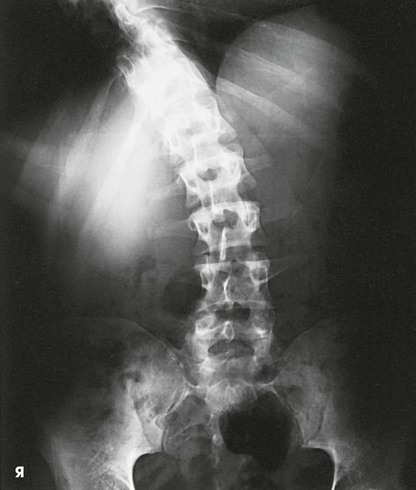

Structures shown, AP and PA

The image shows the lumbar bodies, intervertebral disk spaces, interpediculate spaces, laminae, and spinous and transverse processes (Fig. 8-88). The images may include one or two of the lower thoracic vertebrae, the sacrum coccyx, and the pelvic bones. Because of the angle at which the last lumbar segment joins the sacrum, this lumbosacral disk space is not shown well in the AP projection. The positions used for this purpose are described in the next several sections.

A radiologist may request or prefer that the AP projection be performed with the collimator open to the IR size. This projection provides additional information about the abdomen, in particular when the projection is done for trauma purposes. The larger field enables visualization of the liver, kidney, spleen, and psoas muscle margins along with air or gas patterns (see Fig. 8-88, B). CT and magnetic resonance imaging (MRI) are used often specifically to identify pathology (Fig. 8-89).